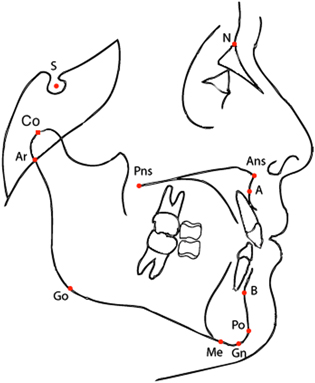

A group of 70 Class III patients (Caucasian ancestry, 7–13 years of age; mean 9.5 years; 40 females and 30 males) from the Graduate Orthodontic Program at the University of Michigan, Ann Arbor, Michigan, and from the Department of Orthodontics, University of Florence, Italy, were analyzed before orthopedic treatment (T1) with rapid maxillary expansion combined with a facial mask (RME/FM). The same patients were re-evaluated (T2, 11–18 years of age, mean 14.7 years) with a lateral cephalogram (see figure 2) following a second phase of treatments with fixed appliances (braces). The patients were matched with a cohort of 70 untreated Class III controls (U2 11–18 years of age, mean 14.5 years) on the basis of race, sex, age, and type of malocclusion. The control patients were selected randomly from a cohort of 1070 Caucasian Class III subjects from the same data sources. All subjects were enrolled previously in large descriptive estimates of craniofacial growth in Class III malocclusion [33, 34] and in two clinical studies [35, 36].

Figure 2. Cephalometric points allow to classify patients according to their cephalogram, i.e. an x-ray of the craniofacial area. Shown in this picture the cephalometric points of the lateral cephalogram used to define the linear distances and angles used in the paper (see table 1).

2.3. Cephalometric analysis

A cephalometric analysis comprising N = 21 variables (10 linear and 11 angular: see table 1 and figure 2) was performed. Data from landmarks contained in each cephalogram were entered into cephalometric software (Dentofacial Planner PlusTM, Version 2.5, Toronto, Ontario, Canada). A standardized enlargement factor (8%) was applied to all linear cephalometric measurements. The error of the method for the cephalometric measurements was evaluated by repeating the measures in 30 randomly selected cephalograms. Error was on average 0.8° for angular measures and 0.9 mm for linear measures.

Table 1. Description of the cephalometric variables used in this paper. Notice that the acronym is often composed by the juxtaposition of the labels of two or three cephalometric points as defined in figure 2; in such a case, it corresponds either to the linear distance among two points, or to the angle defined by the three points.